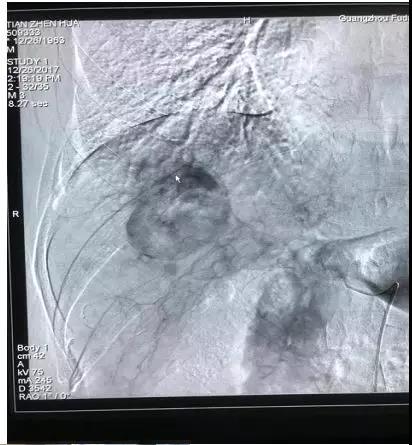

一年后复查田先生肝部肿瘤增大,并出现转移病灶

其实,早在一年前他就查出原发性肝癌,却没有接受任何正规治疗。“都是保健品惹得祸!”意识到事态严重的田先生千里迢迢来找徐克成教授求救。12月26日,田先生在暨南大学附属广州复大肿瘤医院接受血管栓塞介入治疗,目前情况良好。